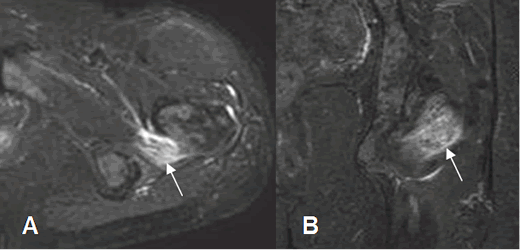

A: RM axial y B: RM coronal en STIR. Imagen ovalada y de consistencia quística en relación con el músculo obturador interno, por bursitis.

Fig 139. Bursitis.